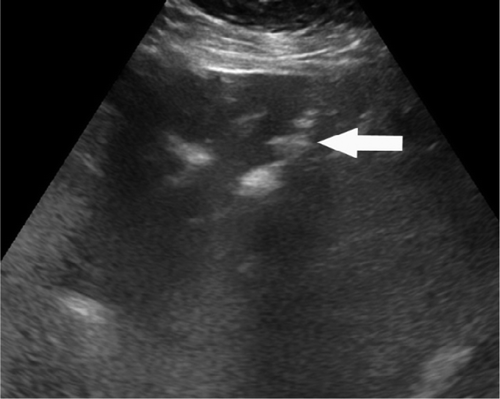

В частности, как пояснил специалист, у некоторых пациентов с COVID-19 внезапно развивался пневматоз - патологическое состояние системы пищеварения, при котором газы проникают в толщу стенки кишечника и образуют там воздушные кисты. Кроме того, у нескольких людей было выявлено необычное желтое обесцвечивание кишечника, еще у трех больных - инфаркт кишечника.

© Radiology